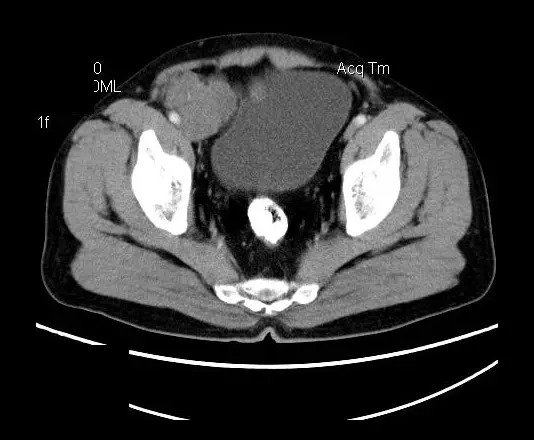

【影像表现】

盆腔右前侧及邻近腹股沟区可见多发大小不等的聚集生长的结节影,病灶呈软组织密度,边缘尚规整,分界尚清,增强扫描可见不均匀强化。膀胱局部受压,盆腔未见明显肿大淋巴结影。

“盆腔”多发性神经鞘瘤